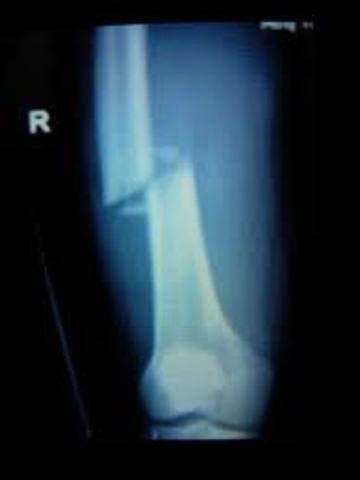

• I broke my femur

I broke my femur

I was playing hockey and i got hit knee on knee and i snapped my femer> I had surgery and three screws put in